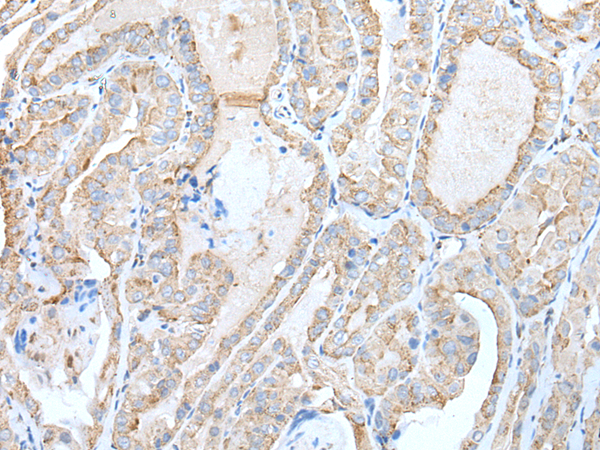

分类: 科研抗体货号: P12749别名: EL52; HSPN; LAP2; HSP86; HSPC1; HSPCA; Hsp89; Hsp90; LAP-2; HSP89A; HSP90A; HSP90N; Hsp103; HSPCAL1; HSPCAL4; HEL-S-65p应用: IHC反应种属: Human, Mouse, Rat